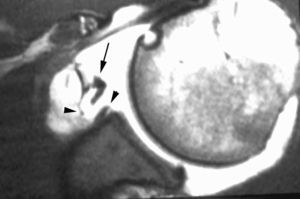

POLPSA (posterior labral periosteal sleeve avulsion)

Esta lesión se asemeja a la ALPSA, pero ocurre en el borde glenoideo posterior. El LG se halla desplazado hacia dentro y por detrás del borde glenoideo posterior. El mecanismo de producción del POLPSA es una dislocación posterior, y por tanto se puede encontrar también un Hill Sachs invertido19 (fig. 14).

. Artrorresonancia axial T1 con supresión grasa donde se observa una rotura del labio glenoideo posterior con desplazamiento posteromedial (flecha). Nótese la situación del labio glenoideo en comparación con una rotura sencilla, no desplazada, que se observa en la figura 13. Obsérvese la presencia de una lesión de Hill-Sachs invertida (cabezas de flecha), en relación con una dislocación posterior con reducción.Lesión de Bennett